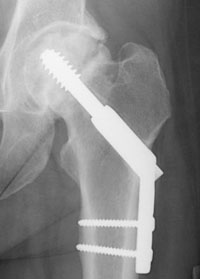

For true intracapsular hip fractures, the surgeon may decide either to fix the fracture with individual screws (percutaneous pinning) or a single larger screw that slides within the barrel of a plate. This compression hip screw will allow the fracture to become more stable by having the broken area impact on itself. Occasionally, a secondary screw may be added for stability.

The compression hip screw is fixed to the outer side of the bone with bone screws and has a large secondary screw (lag screw) that is placed through the plate into the neck and head of the hip (see compression hip screw figure above). The design of the device allows for impaction and compression at the fracture site. This may increase the stability of the area and promote healing.

Repair of an intracapsular fracture with a single compression hip screw.